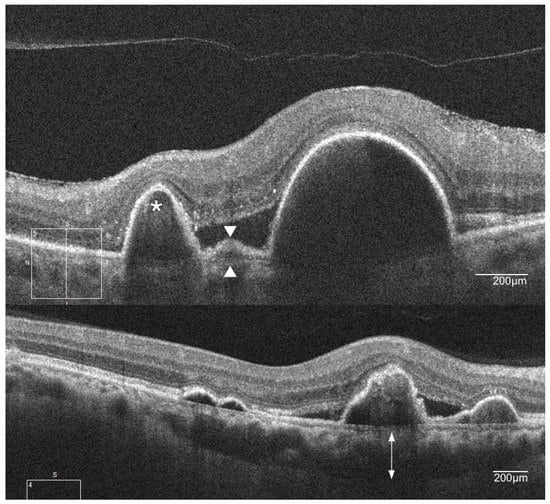

- Giovannini, A.; Amato, G.P.; D’Altobrando, E.; Giuliani, M. Optical coherence tomography (oct) in idiopathic polypoidal choroidal vasculopathy (ipcv). Doc. Ophthalmol. 1999, 97, 367–371. [Google Scholar] [CrossRef] [PubMed]

- Iijima, H.; Imai, M.; Gohdo, T.; Tsukahara, S. Optical coherence tomography of idiopathic polypoidal choroidal vasculopathy. Am. J. Ophthalmol. 1999, 127, 301–305. [Google Scholar] [CrossRef]

- Lee, W.K.; Baek, J.; Dansingani, K.K.; Lee, J.H.; Freund, K.B. Choroidal morphology in eyes with polypoidal choroidal vasculopathy and normal or subnormal subfoveal choroidal thickness. Retina 2016, 36, S73–S82. [Google Scholar] [CrossRef] [PubMed]

- Alshahrani, S.T.; Al Shamsi, H.N.; Kahtani, E.S.; Ghazi, N.G. Spectral-domain optical coherence tomography findings in polypoidal choroidal vasculopathy suggest a type 1 neovascular growth pattern. Clin. Ophthalmol. 2014, 8, 1689–1695. [Google Scholar] [CrossRef] [PubMed]